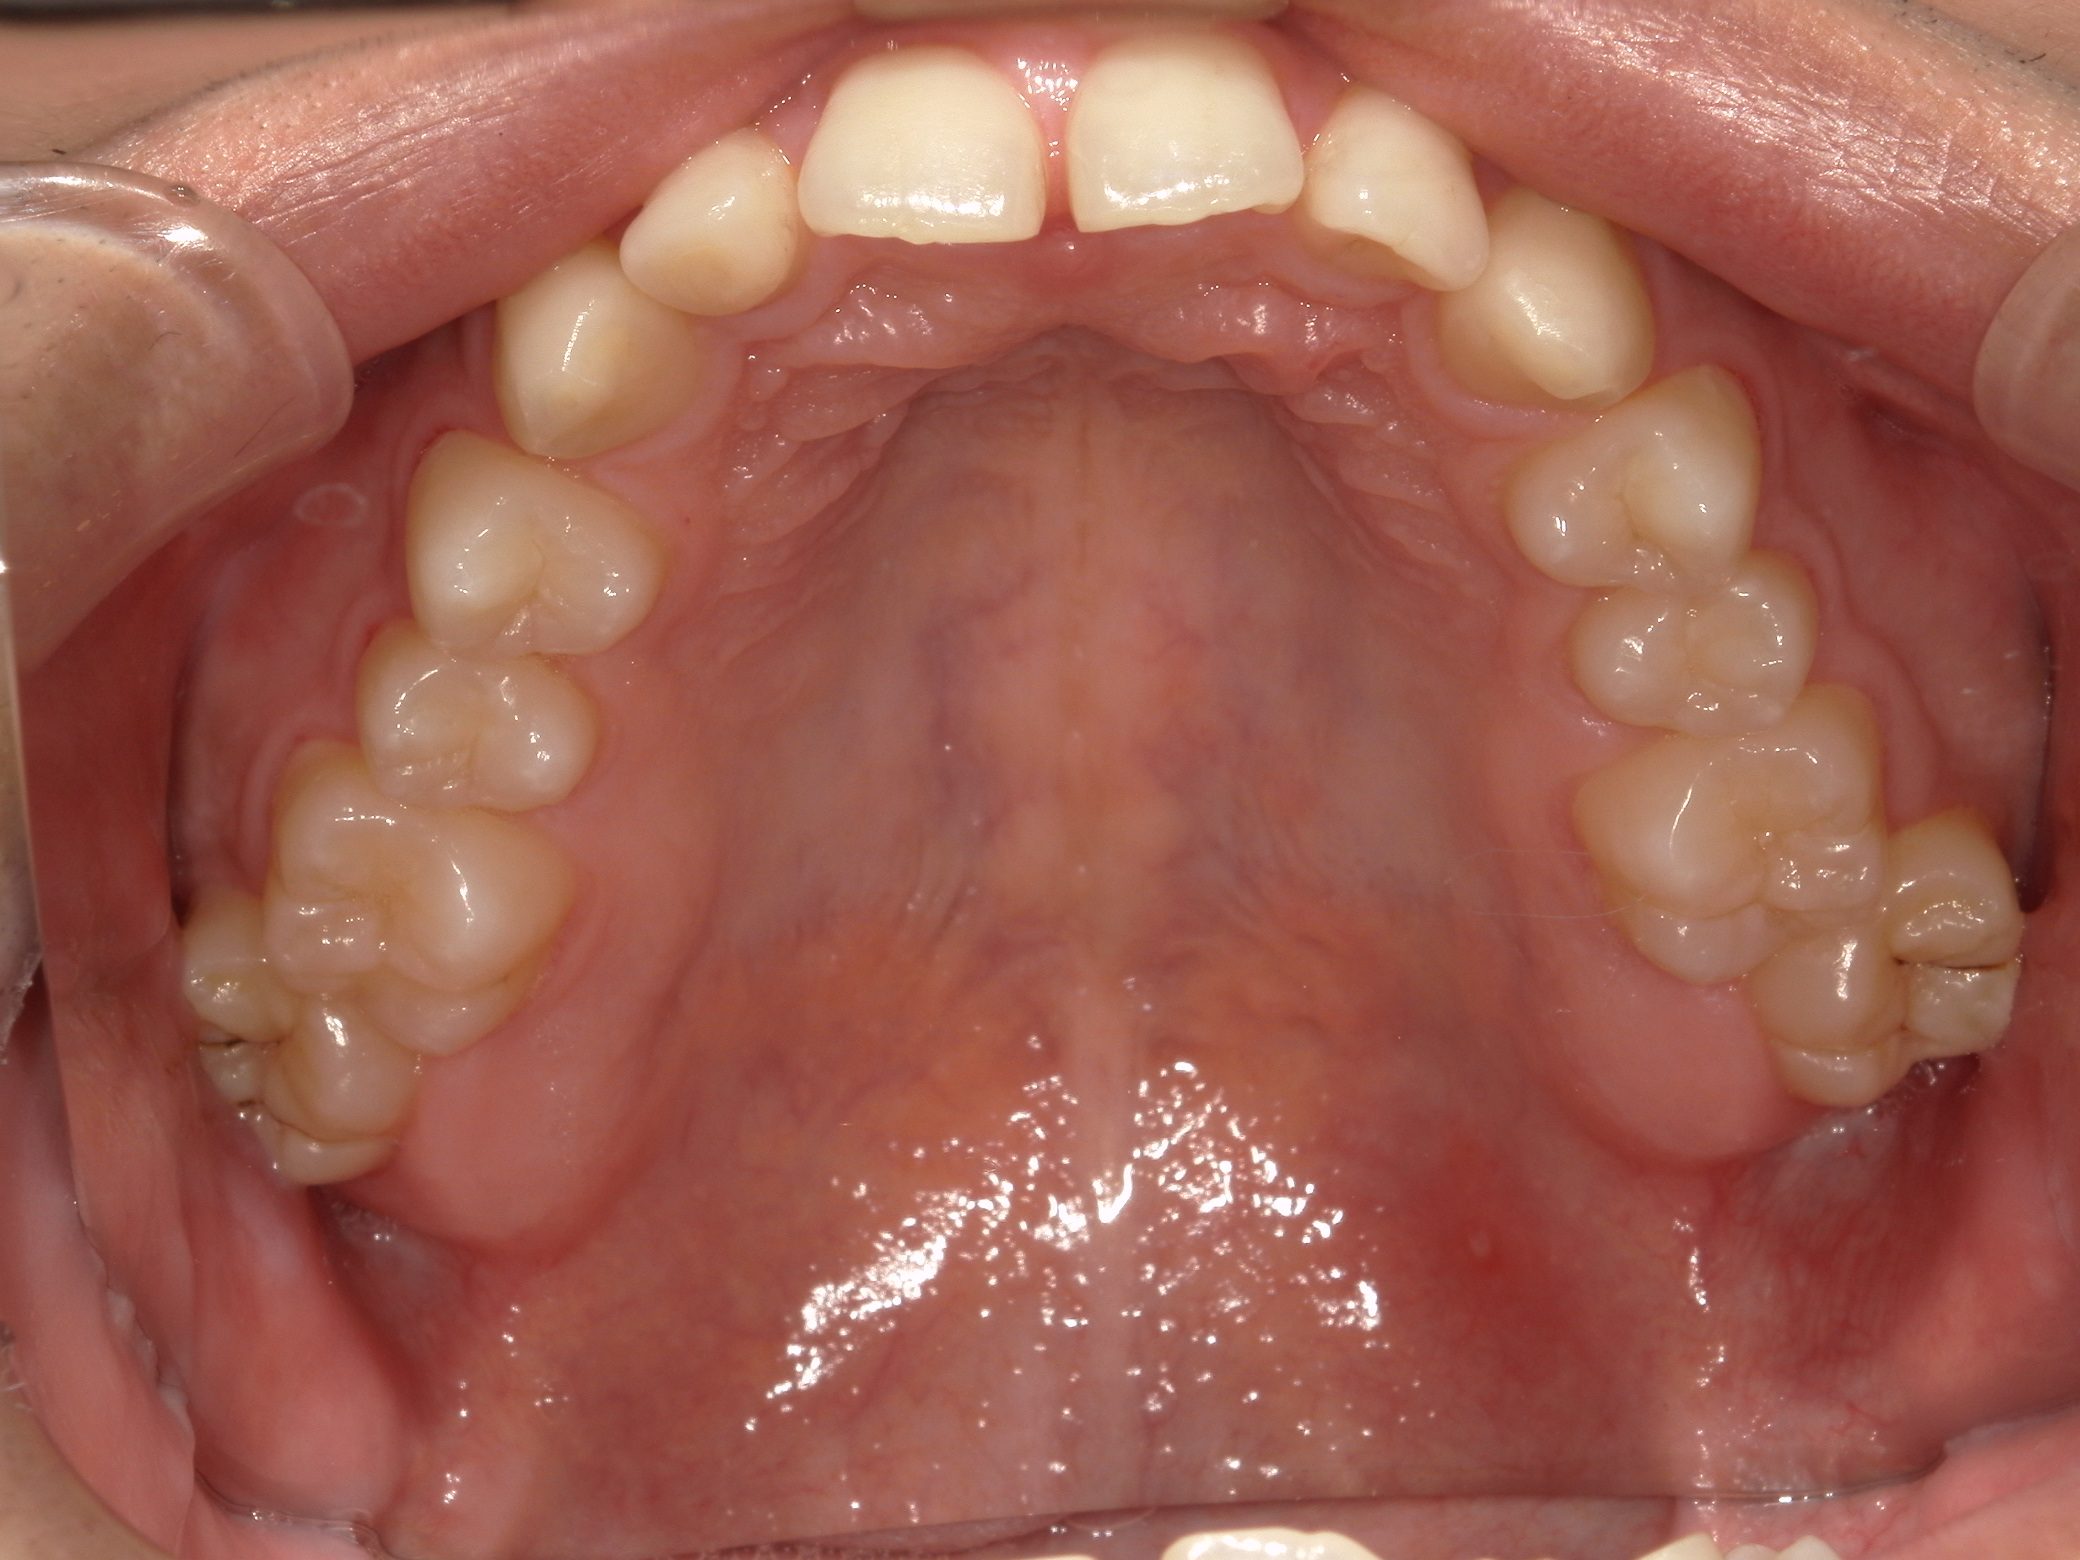

Before

After

治療期間

10か月年

治療開始

19歳

種類

インビザライン矯正

使用装置

インビザラインフル

コメント

すきっ歯なので ディスキングなどもなし

県外の大学に進学されていたので2カ月ごとの来院で10か月で終了

一番奥の歯がすれ違い咬合でしたが、綺麗に治りました。